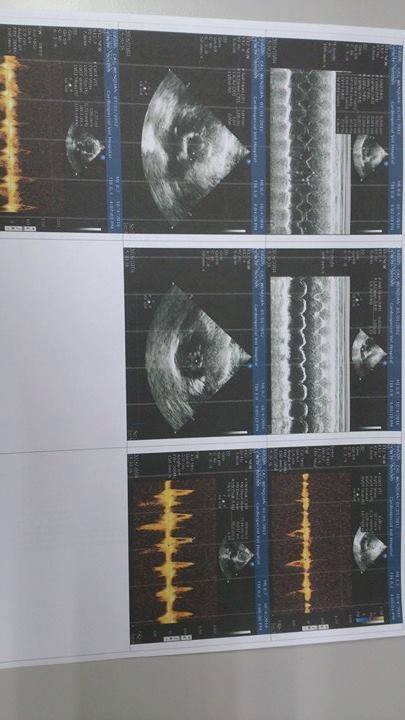

後來發現溫泉的心臟會有顫動的問題,因此需要定期至專心動物醫院回診治療,目前溫泉體重4.15KG,血壓148,並做了心臟X光、血檢、心電圖、心臟超音波等檢查,各項數值皆與之前差不多,顯示維持得不錯,繼續服藥就可以,只是醫生擔心他心臟偶爾會顫動,希望在他平靜的時候,可以幫他側一下心跳,測量方式為:手摸他胸口,測量一分鐘跳幾次,持續側一周,若每分鐘超過160下,則需調整藥量,若沒超過,就繼續保持現狀。